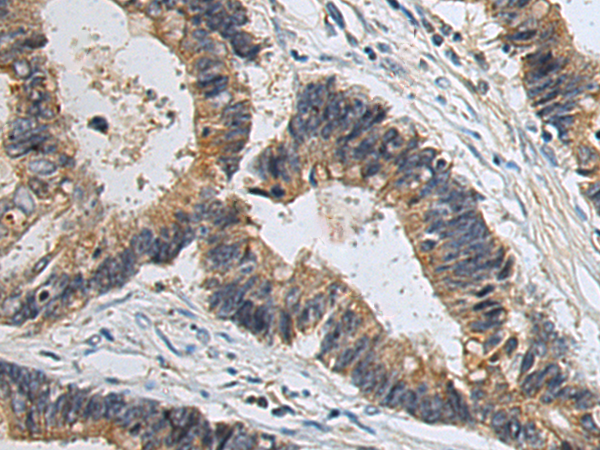

ELISA, WB, IHC

IHC positive control:

Human cervical cancer and Human colorectal cancer

IHC Recommend dilution:

50-100